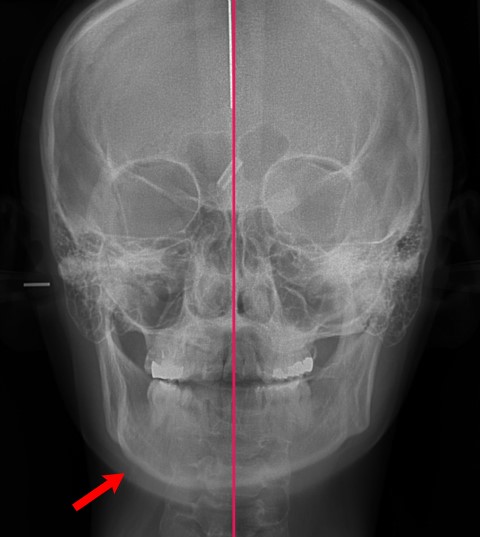

턱비대칭현상

턱이 비대칭인 경우로 좌우를 비교해 봤을 때 붉은 화살표가 가르키는 오른쪽 턱이 훨씬 발달했음을 확인할 수 있습니다. 하악자체가 비틀어진 것이 아닌 단순히 턱의 발달이 짝짝이인 경우로 이는 양악수술이 아닌 안면윤곽수술이 적용되어야 하는 케이스입니다.